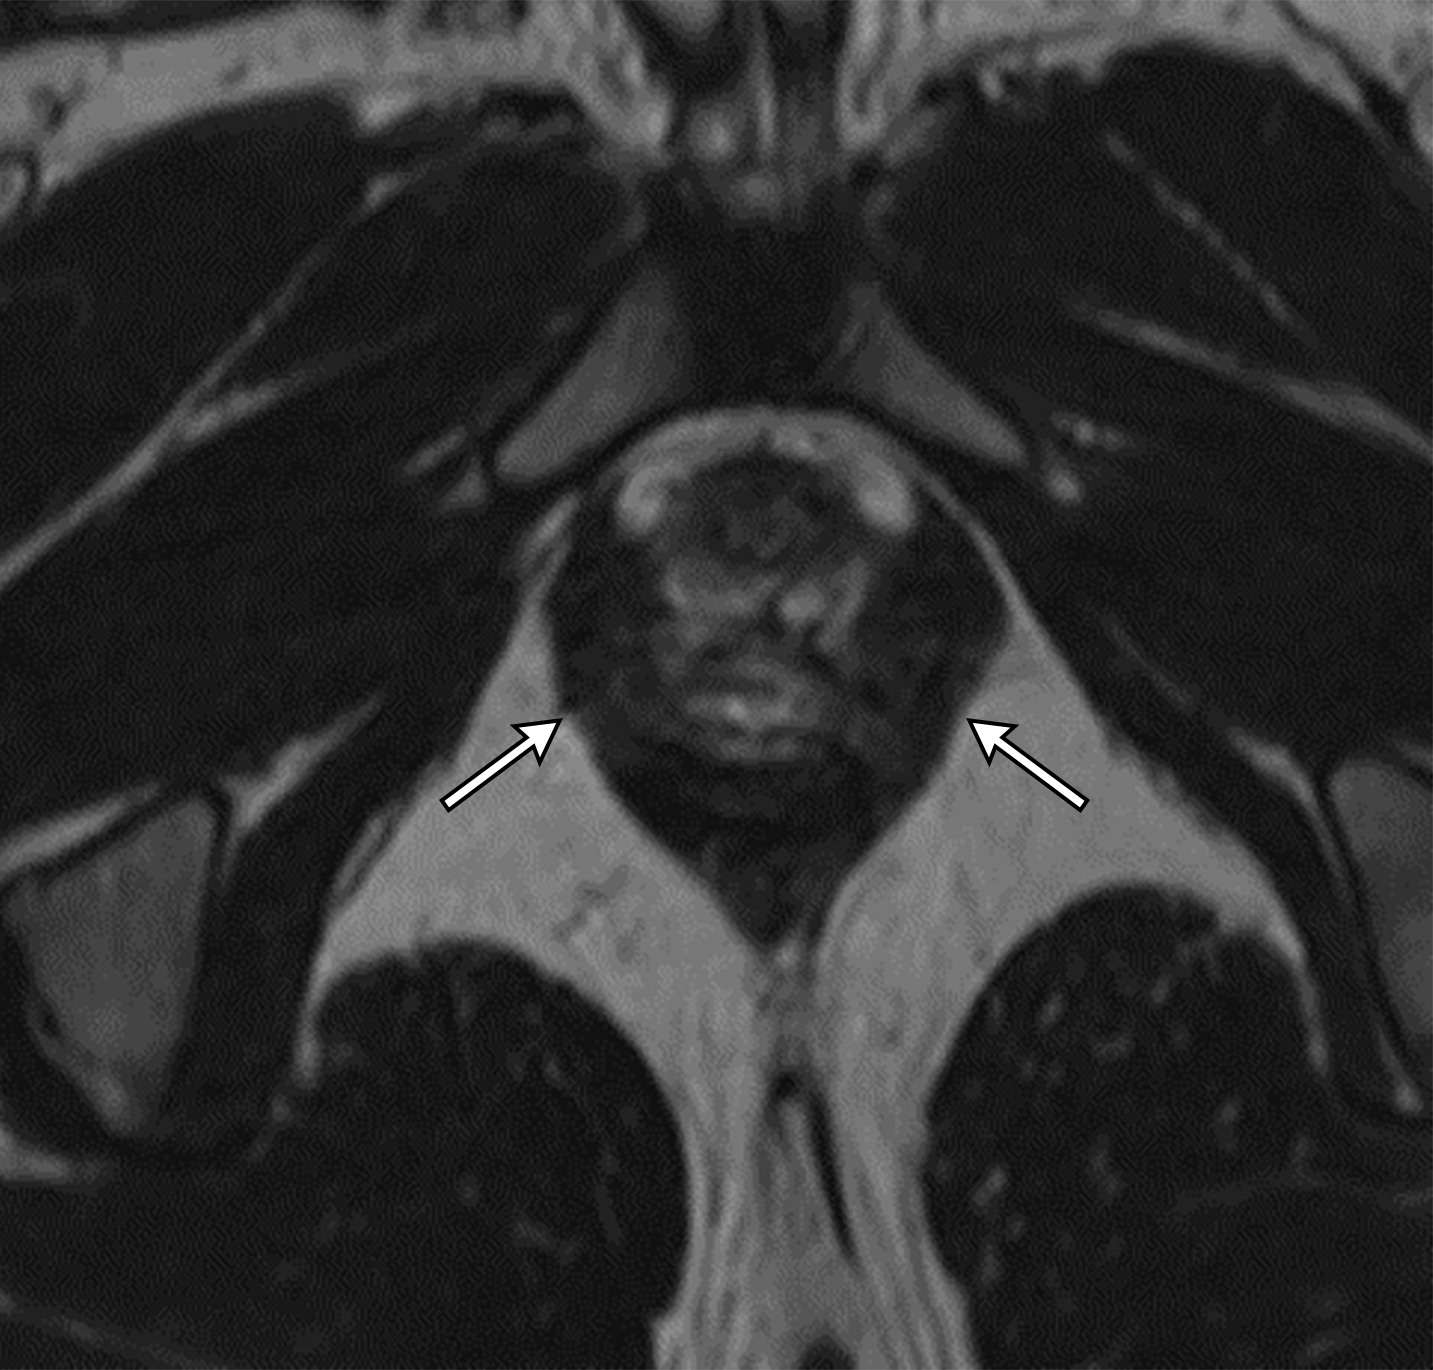

50岁以上男性骨盆和盆底的MRI解剖。

提肛肌(LA),由耻骨直肠肌(PR)、耻骨尾骨肌(PC)和髂尾骨肌(IC)组成;尾骨肌(C),前列腺(P),闭孔内肌(OI),会阴浅横肌(STP),球海绵体肌 (B), 坐骨海绵体肌(ISC),肛门外括约肌(EAS),肛门内括约肌(IAS),直肠(R),尿道括约肌(SU),也称为尿道外括约肌(U),它包围着整个膜性尿道。6774449af17bb1b8df6e83ab4e9fa158.jpeg